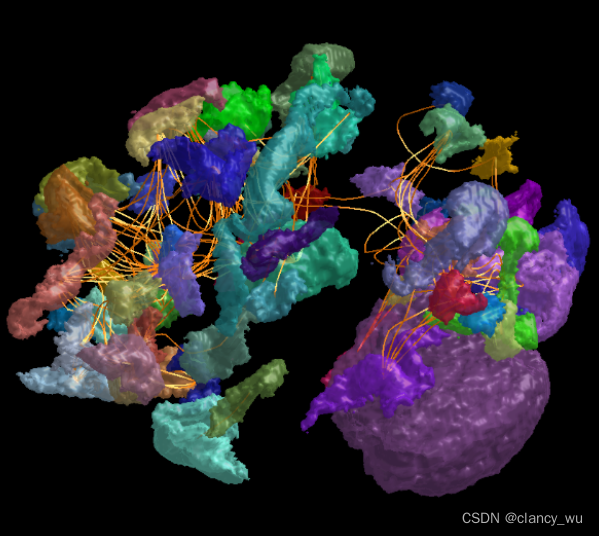

node换成mesh,可视化:

label2mesh hcpmmp1_parcels_coreg.mif hcpmmp1_mesh.obj

这样脑区就不是节点的形式呈现,而是脑区的形状呈现。

连接呈现:

connectome2tck sift_1mio.tck assignments_hcpmmp1.csv exemplar -files single -exemplars hcpmmp1_parcels_coreg.mif

注意,这里的exemplar是自定义的,是输出文件的前缀名称,例如这里生成的是exemplar.tck文件。这可以显示出两个ROI的连接路径,是怎样的形式来连接的。